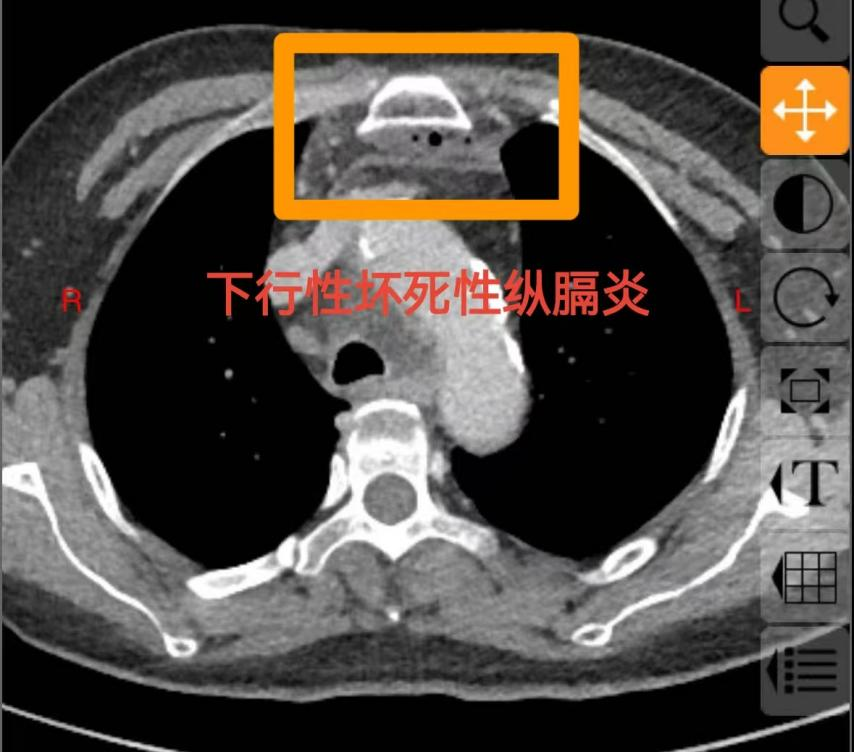

60岁的庄女士未曾想到,一场看似寻常的牙痛,竟会迅速发展为危及生命的重症。庄女士糖尿病多年未经规范治疗,口腔卫生欠佳,口内牙齿时不时疼痛、松动、脱落,患者总认为牙疼是小毛病,吃点甲硝唑就好了,从未重视。5 天前,左下后牙疼痛后患者依旧未经重视,很快就出现咽部、颈部疼痛伴吞咽困难,在当地医院接受抗感染治疗,病情却未见好转,还出现难以忍受的胸部疼痛,叠加吞咽、呼吸困难等症状,被救护车紧急送往西安市红会医院耳鼻咽喉头颈整形修复科。经诊断,庄女士为 “颞下、咽旁、翼下颌、颌下间隙感染,颈部坏死性筋膜炎、下行性坏死性纵膈炎”,病情及其危重,需要头颈外科、胸外科、内分泌科等多学科联合救治,此类疾病非常凶险,死亡率较高,为患者办理住院后转入急诊重症监护室(EICU),一场与死神的赛跑就此拉开序幕。

耳鼻咽喉头颈整形修复科龚龙岗主任、马戈副主任团队第一时间全面评估病情,发现庄女士不仅存在口腔颌面多间隙感染,还并发左侧颈部坏死性筋膜炎、下行性坏死性纵膈炎、右侧包裹性脓胸,叠加2型糖尿病(血糖控制不佳)、高血压病1级(极高危)、电解质紊乱等基础疾病与并发症,病情复杂凶险。面对这一局面,科室迅速启动多学科联合救治机制,一场跨科室的协同作战即刻展开 —— 胸部外科、EICU、内分泌代谢科、神经内科、营养膳食科等科室专家迅速集结,从各自专业维度切入,共同为庄女士制定个性化救治方案。

下行性坏死性纵膈炎